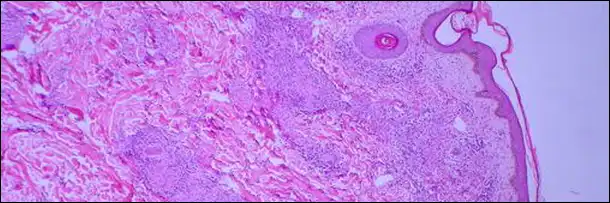

5. Джон Хантер заразил себя венерическим заболеванием

Истории всех предыдущих учёных меркнут по сравнению с тем, на что ради науки решился знаменитый английский доктор Джон Хантер.

Очевидно, что Хантеру приходилось лечить толпы пациентов с венерическими заболеваниями. К тому времени все уже знали, что эти болезни передаются половым путём, но как они развиваются и как связаны друг с другом – никто понятия не имел.

Наблюдая пациентов, больных сифилисом и гонореей, Хантер выдвинул гипотезу, согласно которой оба заболевания вызываются одним и тем же возбудителем. Он считал, что это, в сущности, одно и то же заболевание, но на разных стадиях.

Для того, чтобы доказать верность своей теории, Хантеру нужно было привить гонорею кому-нибудь, кто точно никогда не болел ни одним из венерических заболеваний. И если испытуемый заболеет гонореей (к тому времени он уже решил, что этим кем-то станет сам), и у него не обнаружится никаких симптомов сифилиса – будет ясно, что это разные заболевания.

Хантер привил себе выделение из уретры больного гонореей, после чего у него обнаружились признаки сифилиса (к счастью, болезнь потом удалось благополучно вылечить препаратами ртути). Теория, казалось бы, была доказана.

Но…

Оказалось, что игла, которой Хантер делал себе прививку гонореи, была уже к тому времени заражена сифилисом. Учёный об этом не знал и когда заболел обеими болезнями, посчитал свою ошибочную теорию верной.